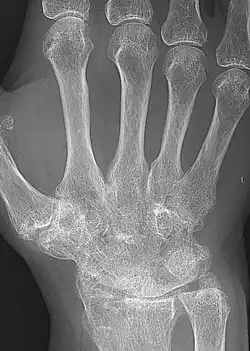

X-ray of the hand in rheumatoid arthritis

X-rays of the hands and feet are generally performed when many joints are affected. In RA, there may be no changes in the early stages of the disease, or the X-ray may show osteopenia near the joint, soft tissue swelling, and a smaller than normal joint space. As the disease advances, there may be bony erosions and subluxation. Other medical imaging techniques such as magnetic resonance imaging (MRI) and ultrasound are also used in RA.[20][79]

Technical advances in ultrasonography, like high-frequency transducers (10 MHz or higher), have improved the spatial resolution of ultrasound images, depicting 20% more erosions than conventional radiography. Color Doppler and power Doppler ultrasound are useful in assessing the degree of synovial inflammation as they can show vascular signals of active synovitis. This is important since in the early stages of RA, the synovium is primarily affected, and synovitis seems to be the best predictive marker of future joint damage.[80]